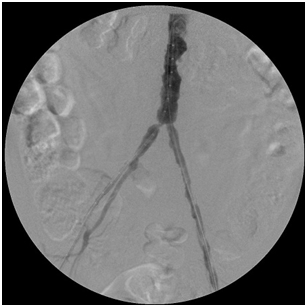

The images below illustrate such a problem. This patient in addition to having irregular chunks of calcium narrow his aorta has significant narrowing of the origins of his common iliac arteries (ostial stenosis), which along with the narrowings above and below them diminished the amount of blood reaching the patient’s feet from the aorta, causing symptoms.

By simultaneously deploying a stent across each common iliac ostial narrowing, I corrected the problem, delivering more blood into the patient’s feet. The first image shows the narrowings before the stents were deployed; the second image displays the process of stent deployment; the third image was taken after I landed the stents.